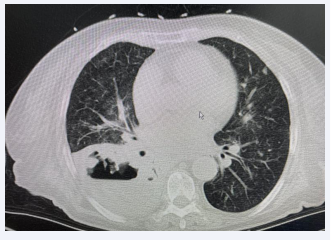

Laboratory tests revealed a white blood cell count of 12*109 /L, with a neutrophil percentage of 76%, and an elevated C-reactive protein level of 232 mg/L. The lung cancer marker cytokeratin 19 fragment (CYPRA21-1) was elevated at 6.44 ng/L (normal range 0–3.3 ng/ml). Sputum cultures and blood cultures yielded negative results for pathogenic microorganisms. CT scan of the chest revealed bronchial wall thickness in the upper and middle lobes of the right lung, along with bronchial changes in the middle and lower lobes of the right lung. Inflammation was observed in both lungs, particularly in the significant lower lobe of the right lung, featuring a combined lung abscess. Enlarged right hilar and mediastinal lymph nodes, as well as right-sided pleural effusion, were evident (Figure 1).

Lung CT imaging (soft tissue window).

Figure 1: Lung CT imaging (soft tissue window).